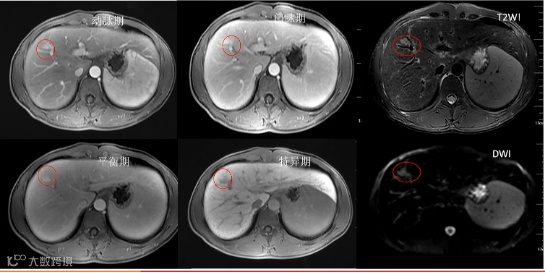

患者女性,59岁,HBV相关肝硬化。病例中scHCC显示出HCC的所有诊断特征,但门脉期无廓清,根据2024版原发性肝癌指南,对于EOB-MRI移行期或肝胆期“快出”也可作为辅助恶性征象,因此考虑scHCC,病理证实Edmondson-Steiner II级HCC[5]。

a:T2WI高信号,b:DWI弥散受限,c:动脉期非环形强化,d:门脉期无明显廓清,e:过渡期低信号,f:移行期低信号,直径为7.3mm[5]。